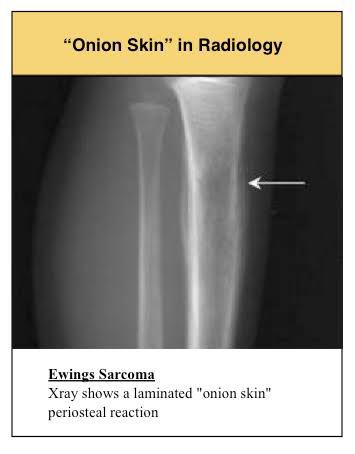

Characteristic feature of ewing sarcoma

Characteristic feature of ewing sarcoma radiologically is inion skin appearance

Ewing Sarcoma